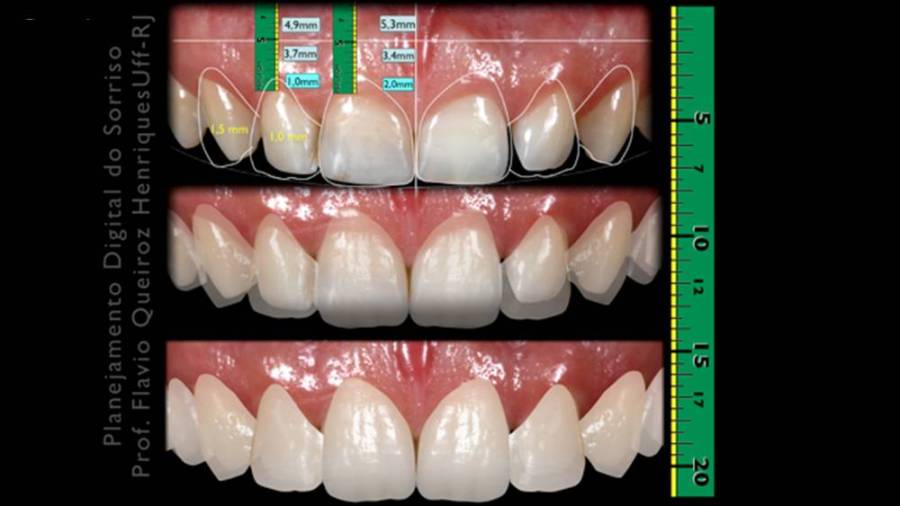

ესთეტიკურ სტომატოლოგიაში არსებობს კომპიუტერული პროგრამები, რომელიც სწორედ ფოტოსურათებზე დაყრდნობით მისაღები შედეგის მოდელირების საშუალებას იძლევა, რაც პაციენტისთვისაც და ექიმისთვისაც მკურნალობის გეგმის შედგენისას ორიენტირს წარმოადგენს.

ფოტოების გადაღება ხდება მკურნალობამდე, შემდეგ კი მათი დეტალური ანალიზი პროგრამის საშუალებით და ციფრული მოდელის შექმნა. ერთერთი ასეთი პროგრამაა DSD –Digital Smile Design. მისი საშუალებით შესაძლებელი არამარტო კოსმეტიკური სამუშაოს, არამედ იმპლანტაციის დაგეგმვაც.